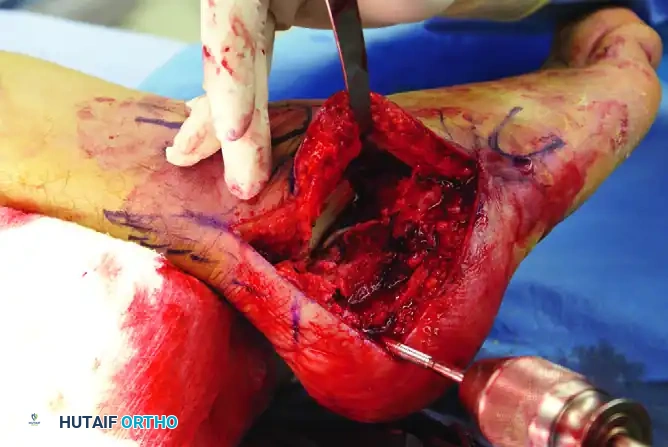

The extensile lateral approach provides unparalleled access to the lateral wall, posterior facet, and calcaneocuboid joint.

- Incision Design: Outline the anatomical landmarks. The vertical limb of the incision is placed just anterior to the lateral border of the Achilles tendon. The horizontal limb is placed in the glabrous skin junction, parallel to the plantar surface of the foot.

- Execution: Carry the incision directly down to the periosteum of the lateral calcaneal wall in a single, decisive stroke.

- Sural Nerve Protection: Crucial Step. Do not perform blunt soft tissue dissection in the midportion of the wound. The sural nerve crosses the incision at its proximal and distal ends; meticulous, sharp soft tissue dissection should be reserved strictly for these terminal areas to identify and protect the nerve.

Gently retract the corner of the flap while initiating subperiosteal dissection along the lateral wall.

It is essential to follow the contours of the blown-out lateral wall. Do not stray into the subcutaneous soft tissues, as this will damage the peroneal tendons and compromise the vascularity of the flap. The peroneal tendons and the sural nerve must remain contained within the full-thickness flap.

Elevate the entire flap en bloc. To maintain exposure without causing crush injury to the flap edges (which occurs with self-retaining retractors), utilize the "no-touch" Kirschner wire (K-wire) retraction technique.

- Place stout K-wires (1.6 mm or 2.0 mm) longitudinally into the fibula, the lateral aspect of the talus neck, and the cuboid.

- Bend these wires backward to act as a scaffold, gently holding the full-thickness flap out of the surgical field. Once secured, the flap does not need to be touched again for the remainder of the procedure, drastically reducing the risk of marginal necrosis.

- Expose the entire lateral wall of the calcaneus distally to the calcaneocuboid joint. If necessary, carry the dissection above and below the peroneal tendons at the level of the calcaneocuboid joint to ensure complete visualization.

Step 1: Lateral Wall Mobilization

Once exposure is complete, the blown-out lateral wall fragment will block direct observation of the depressed posterior facet.

* Carefully osteotomize or mobilize the lateral wall.

* Remove it from the surgical field and place it in a secure location on the back table (e.g., wrapped in a moist saline sponge) for later replacement.